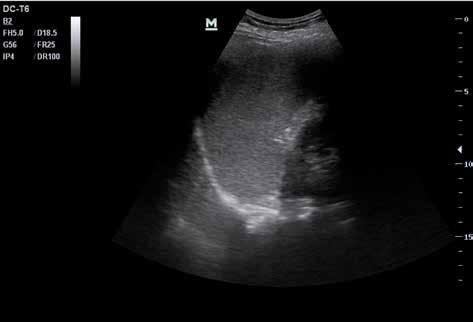

Abb. 34 ˘ Morison-Pouch (1) zwischen Leber (2) und rechter Niere (3). Rechtsseitiger Flankenschnitt 1 2 3

Abb. Abb.

44 4 ˘ Pathologische Befunde

36 ˘ Douglas-Raum (1) dorsal der Blase (2). Unterbauchlängsschnitt

35 ˘ Koller-Pouch (1) zwischen Milz (2) und linker Niere (3). Linksseitiger Flan kenschnitt 3 2 1 21

Zunächst sammelt sich mögliche freie Flüssigkeit an drei typischen präformierten Stel len im Bauchraum und kann hier sonografisch dargestellt werden. Dies sind der MorisonPouch, der Koller-Pouch und der Douglas-Raum (von engl. „Pouch“ für „Beutel“, Abb. 34 –36).

Der Morison-Pouch ist eine Aussackung des Peritoneums zwischen Leberunterrand und rechter Niere. Dem entspricht auf der Gegenseite der Koller-Pouch zwischen Milz und linker Niere. Der Douglas-Raum befindet sich dorsal hinter der Harnblase und zieht bis ins kleine Becken.

Abb. 37 ˘ Freie Flüssigkeit (FAF) (1) im Morison-Pouch. Rechtsseitiger Flankenschnitt Abb. 38 ˘ Freie Flüssigkeit (FAF) (1) im Koller-Pouch. Linksseitiger Flankenschnitt

46 4 ˘ Pathologische Befunde

1 1